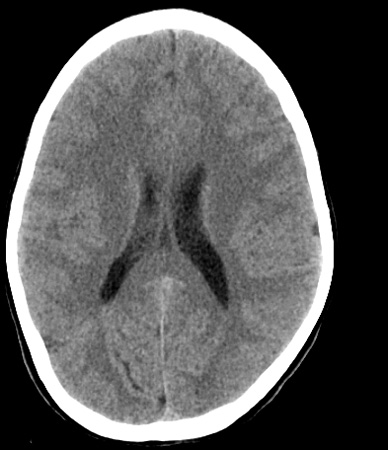

Identify the following structures in the head CT. To view the location of the structure in the image click on the label at the left and an arrow will point to the structure in the image.

Body of the Lateral Ventricle

Falx Cerebri

Occipital Lobe

Corpus Callosum (Splenium)

Superior Sagittal Sinus